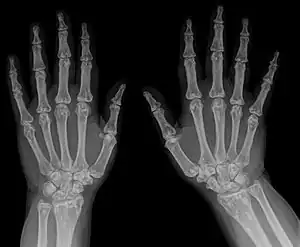

| Diagnostic method | X-ray, ultrasound[4] |

It is a genetic disorder associated with LEMD3.[6][7] It is inherited in an autosomal dominant manner.[2] In a very few, X-rays may show several areas of compact bone.[1] Conditions that may appear similar include tuberous sclerosis, pseudoxanthoma elasticum, neurofibroma, and lipoma, among others.[1]

- X-ray

Note thickened sclerotic cortical bone